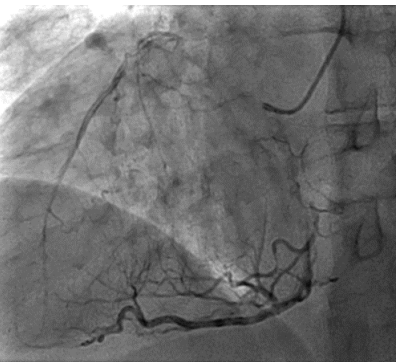

The patient then underwent elective coronary angiography which showed a Normal Left Main,  100% occluded Left Anterior Descending Artery, filling from right sided collaterals, a proximal 80% in the left circumflex with a 99% occluded OM1. The RCA had a proximal 80% lesion with a diffusely diseased acute marginal branch.

Figure 3 RAO caudal view showing disease in the proximal and distal LCX as well in the proximal OM